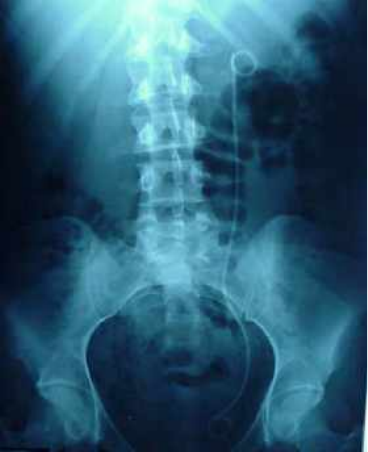

FOTO 5 catéter doble J izquierdo.